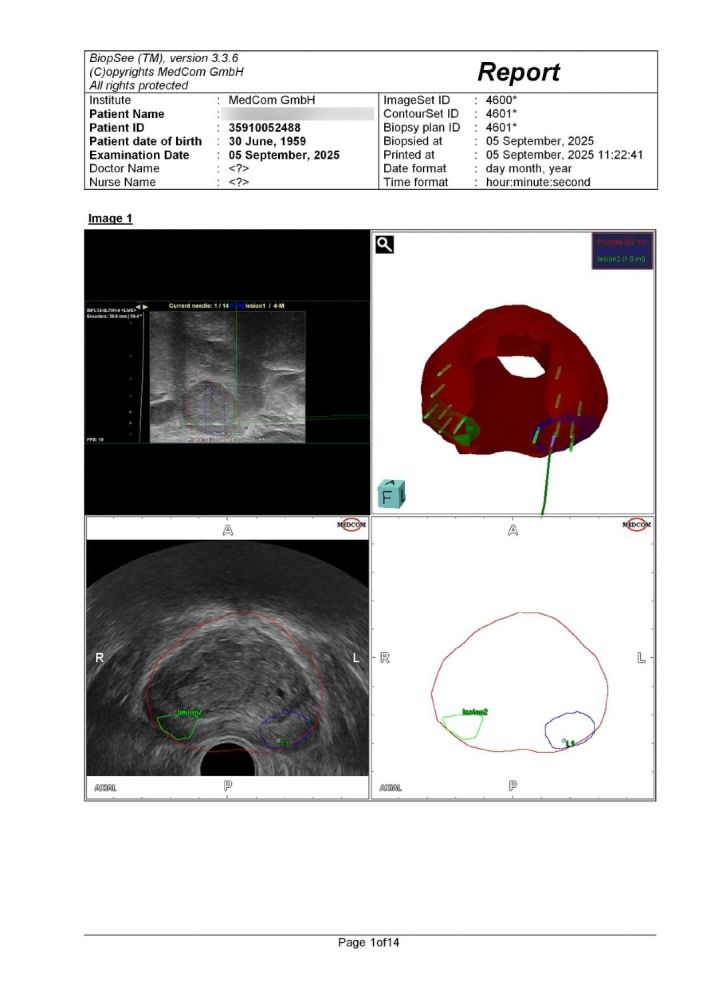

Η λήψη του δείγματος συνήθως πραγματοποιείται με τοπική αναισθησία στην περιοχή του περινέου, αλλά μπορεί να γίνει και υπό γενική αναισθησία, εφόσον το κρίνει απαραίτητο ο Ουρολόγος. Ο γιατρός θα τοποθετήσει μια κεφαλή υπερήχων μέσα στο ορθό, προκειμένου να έχει συνεχή εικόνα του προστάτη αδένα.

Με τη χρήση της κεφαλής, ο γιατρός καθοδηγεί τη βελόνα βιοψίας στον προστάτη και αφαιρεί τα δείγματα που είναι απαραίτητα για τον προσδιορισμό του προβλήματος. Ενδέχεται να πάρει δείγματα και από άλλα σημεία του προστάτη, εφόσον το κρίνει απαραίτητο. Η διαδικασία συνήθως διαρκεί γύρω στα 30 με 45 λεπτά και μπορείτε να επιστρέψετε στο σπίτι την ίδια ή την επόμενη ημέρα.

Αναφορά του συστήματος Biopsee όπου φαίνονται οι στοχευμένες βιοψίες στις βλάβες (δε) & (αρ) που μας εδειξη η Πολυπαραμετρικη MRI προστάτη , όπως και κάποιες στοχευμένες άμφω.